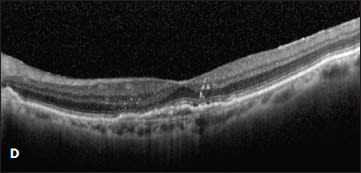

She was then switched to monthly ranibizumab. The subretinal fluid resolved with one injection, and her vision improved to 20/30. However, after nine injections of monthly ranibizumab, her vision declined to 20/40, with a small amount of intraretinal fluid and an enlarging PED (Figure 2C). This visit coincided with the commercially availability of aflibercept, and the treatment was changed to monthly 2.0 mg aflibercept. After two injections, her vision improved to 20/30, the PED flattened, and the subretinal fluid resolved (Figure 2D).

Figure 2. A new occult CNV with PED (A). After treatment with bevacizumab, OCT showed persistent subretinal fluid (B). The therapy was switched to ranibizumab, and after nine injections, the PED had slightly grown in size, but the subretinal fluid had resolved (C). Due to PED growth, the patient was switched to aflibercept, and after two injections, the subretinal fluid resolved, and the PED flattened (D).